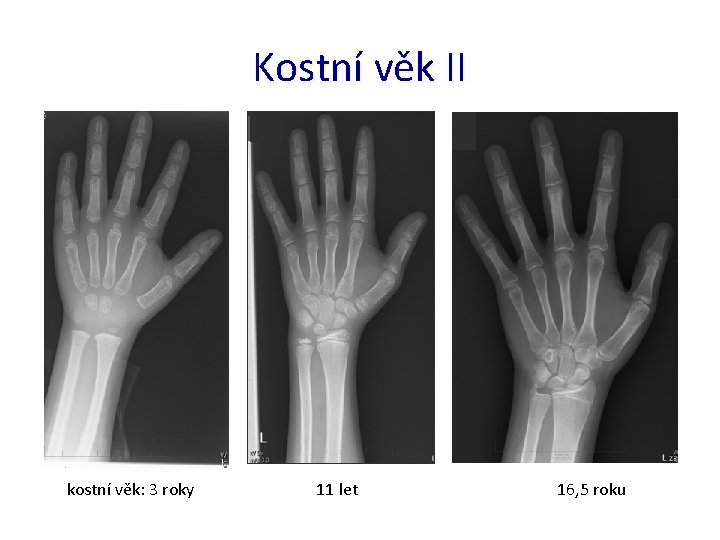

Kostní věk I • ukazatel biologického věku, určuje stupeň zralosti kosti • zjišťován na základě RTG snímku ruky a distální části předloktí levé HK • nejčastější metody: – Greulich-Pyle • porovnání rentgenogramu s fotografickými standardy – Tanner-Withause (TW 1, TW 2, TW 3 – 2001) • hodnocení tvaru, velikosti osifikačních center 20 kostí a jejich vzájemného vztahu (RTG z 76 cm) • R, U, MTC I. , III. a V. , ph. prox. I. , III. a V. , ph. med. III. a V. , ph. dist. I. , III. a V. , ossa carpalia 7

Kostní věk II kostní věk: 3 roky 11 let 16, 5 roku

Kostní věk v endokrinologii pacient – chlapec 7 letá prohlídka výška pod 3. percentilem KV – 2 roky závěr – opožděný kostní věk růst do výšky je v pořádku